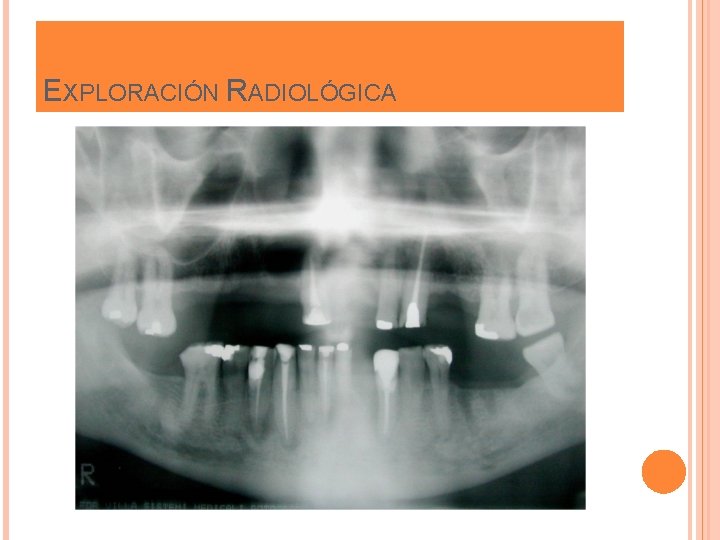

EXPLORACIÓN RADIOLÓGICA

EXPLORACIÓN CLÍNICA Y RADIOLÓGICA Valoración de los dientes pilares Longitud del espacio edéntulo Forma del reborde alveolar Oclusión Estética